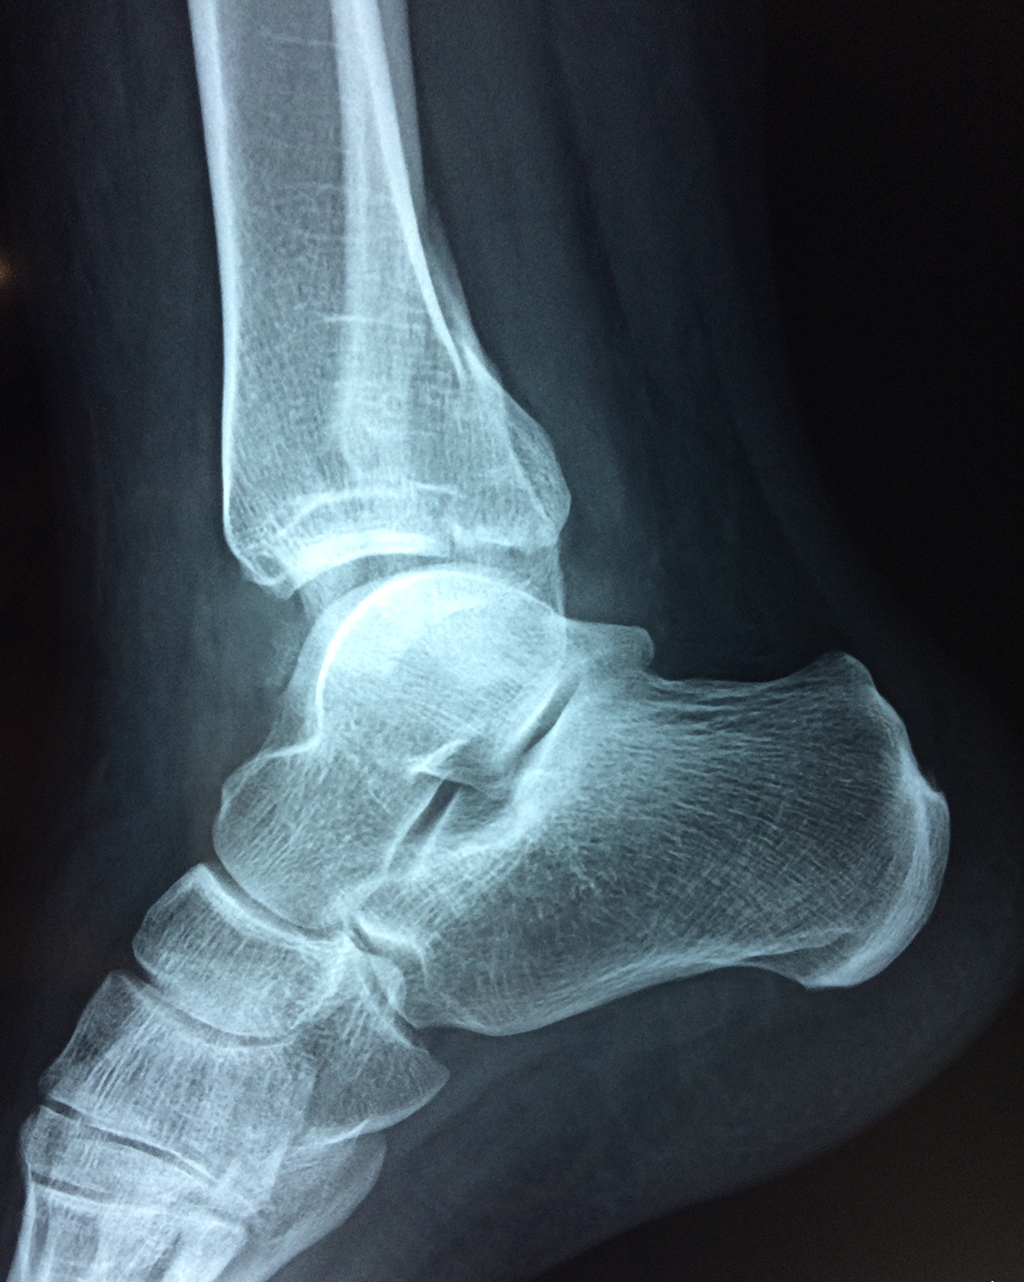

Una fractura de tobillo es la rotura de uno o más de los huesos del tobillo. Estas fracturas pueden ser:

- Parciales (el hueso está sólo parcialmente fisurado, no del todo).

- Completas (el hueso está perforado y está en 2 partes).

- Producirse en uno o ambos lados del tobillo.

- Los extremos de los huesos están desalineados entre sí (desplazados).

- La fractura se extiende hasta la articulación del tobillo (fractura intra-articular).